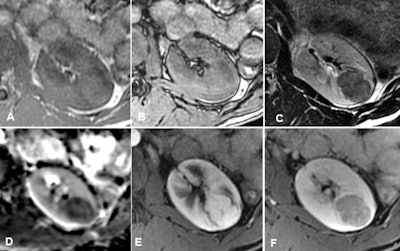

Aspect typique d'un carcinome à cellules claires montrant, comparé au parenchyme rénal normal, une intensité de signal élevée en T2 (A), un coefficient de diffusion apparent élevé (ADC) (B), une chute de signal sur l'image en opposition de phase (D), par rapport à l'image en phase (C) et une vascularisation élevée sur l'image dynamique rehaussée (E). Image reproduite avec l'aimable autorisation de Pr Nicolas Grenier.Les chercheurs espèrent en particulier utiliser les données de la vaste étude prospective pour évaluer pour évaluer les capacités de l'IRM-mp à différencier les tumeurs rénales de petite taille, solides et malignes des tumeurs bénignes, ainsi que pour vérifier la reproductibilité et les effets sur les décisions cliniques et la gestion tumorale, ainsi que pour définir les critères permettant la classification des lésions.

- La séquence pondérée en T2 : elle doit absolument être réalisée en turbo ou fast spin-écho et jamais en T2 rapide en écho de gradient. Elle permet d'évaluer l'intensité de signal de la tumeur par rapport au rein : seuls les fpAML et les CP ont un signal très inférieur à celui du rein.

- La séquence pondérée en T1 en écho de gradient avec étude du déplacement chimique (Dixon) : une chute de signal peut s'observer en opposition de phase en cas de fpAML, de carcinome à cellules claires (CCC) ou de CP, et en phase en cas de CP.

- La séquence de diffusion : seuls les fpAML et les CP ont un signal très inférieur à celui du rein.

- La séquence dynamique après injection de produit de contraste permettant de « tracer » une dynamique de rehaussement : seuls les CP présentent un rehaussement très faible et très progressif.